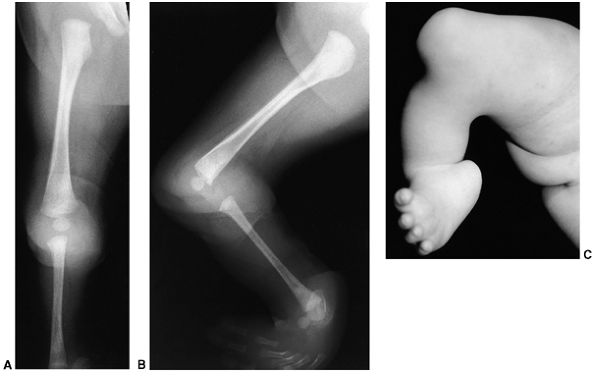

Figure 31.6 A, B: Radiographs of an infant with a type I tibial deficiency of Kalamchi and Dawe (99) (type 1a of Jones et al.) (120),

in which the entire tibia is absent. There was no extensor mechanism and no proximal tibia. If there were a proximal remnant of tibia that would later ossify, this would be a type 1b deficiency of Jones et al. C: The clinical appearance, with the medial deviation and severe equinus of the foot and the absence of any tibial structure below the distal femur. |

deficiency is a markedly shortened tibia with a rigid

equinovarus-supinated foot pointing toward the perineum (Fig. 31.6C).